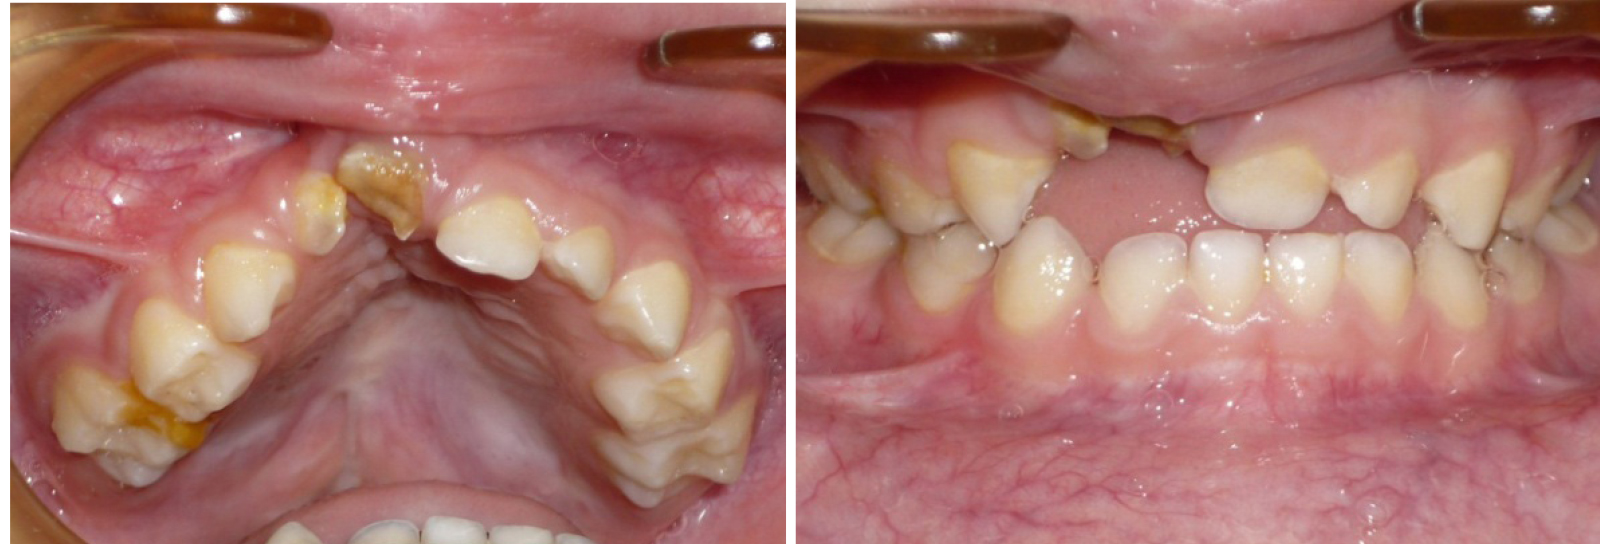

Эффективность предложенных методов графического построения прогнозируемых форм зубных арок определялась при анализе результатов лечения детей с врожденной аномалией в периоде молочного прикуса. С этой целью проведено лечение 15 детей с врожденным односторонним несращением губы и нёба. Практически во всех клинических случаях определялось сужение трансверсальных размеров, более выраженное в переднем сегменте арки. Окклюзия не соответствовала признакам физиологической нормы. Отмечалось укорочение глубины арки (рис. 2).

Лечение проводилось с применением несъемной дуговой аппаратуры. Фиксирующими элементами служили тонкостенные коронки (кольца) с припаянными вестибулярными брекетами. Размер металлической дуги определяли с помощью предложенных методов графического анализа (рис. 3). Металлические дуги меняли с учетом протокола лечения эджуайс-техникой до нормализации формы арки, соответствующей прогнозируемым размерам. После нормализации окклюзионных взаимоотношений аппарат использовался в качестве ретенционного до смены молочных зубов постоянными (рис. 4).

Анализ данных биометрии показал, что на стороне расщелины расстояние от условной сагиттали до молочного клыка составляло до лечения (11,52 ± 0,93) мм, а после лечения исследуемый параметр составлял (16,39 ± 0,64) мм (р ˂ 0,05). На котрлатеральной стороне разница в изменении положения клыка была не достоверной и в динамике лечения изменялась с (14,93 ± 0,79) до (16,27 ± 0,84) мм (р ˃ 0,05). Отмечалось изменение размеров диагоналей переднего сектора дентальных арок (клыковых диагоналей), которые на стороне расщелины в динамике изменялись от (13,34 ± 0,96) до (18,27 ± 0,71) мм (р ˂ 0,05). На контрлатеральной стороне исследуемый показатель изменялся с (16,73 ± 0,87) до (18,12 ± 0,95) мм (р ˃ 0,05). Диагонали зубных дуг (центрально-молярные) с обеих сторон после лечения составляли по (35,52 ± 1,13) мм.